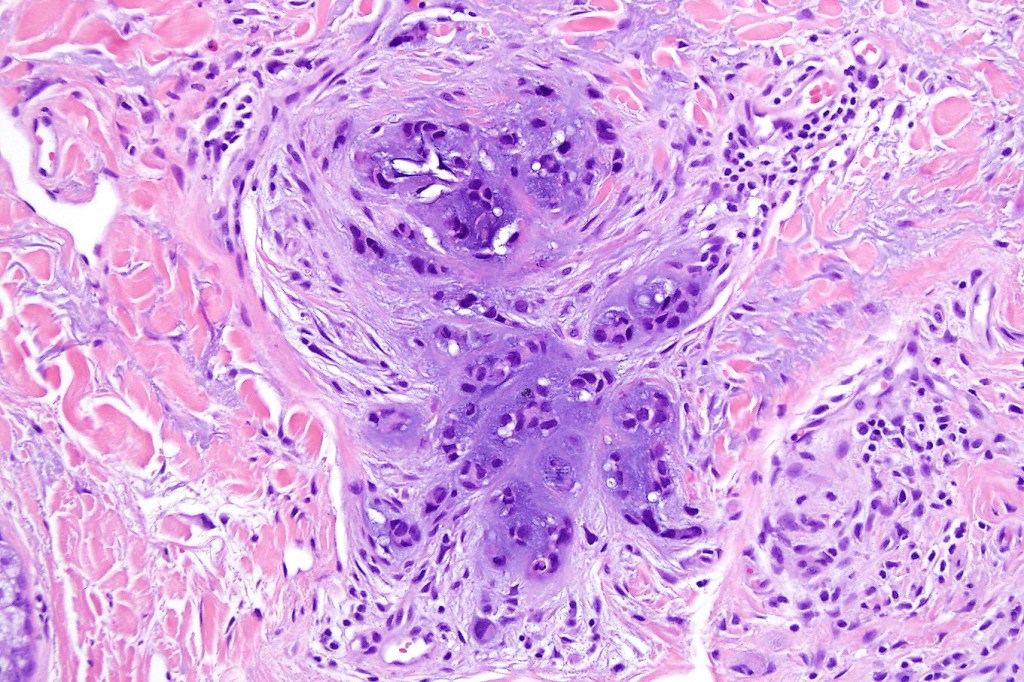

•Well circumscribed unencapsulated, nodular/multinodular silhouette composed of an admixture of epithelial & mesenchymal elements

•Often intensely basophilic due to mucinous deposits

•Stromal sclerosis & hyalinization

•Myxoid change

•Chondroid foci